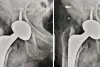

Read More... 96 वर्षीय महिला का किया सफल हिप रिप्लेसमेंट, गिरने की वजह से फ्रेक्चर

उन्नत आधुनिक तकनीक, और बेहतर विश्वस्तरीय सुविधाओ की उपलब्धि के कारण जीवन के अंतिम पड़ाव में भी लोग जोड़ प्रत्यारोपण सर्जरी करवाकर आत्म सम्मान और आत्म निर्भरता का जीवन जीने में सफल हो रहे है।